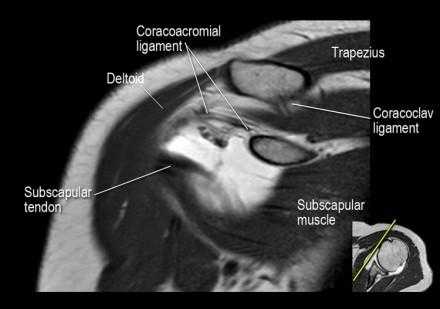

Изображение передних отделов плечевого сустава.

Сухожилие подлопаточной мышцы прикрепляется как к малому бугорку, так и к большому бугорку, давая поддержку длинной головке двуглавой мышцы в борозде двуглавой мышцы. Вывих длинной головки двуглавой мышцы плеча неизбежно приведет к разрыву части подлопаточной сухожилия. Манжета вращателей плеча состоит из сухожилий подлопаточной, надостной, подостная и малой круглой мышц.

Нормальная корональная анатомия плечевого сустава и контрольный список

- обратите внимание на клюво-ключичную связку (coracoclavicular ligament) и короткую головку двуглавой мышцы (short head of the biceps).